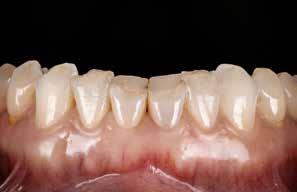

(Fig. 6 A-D). Relativt flad Spee kurve. Ud fra TWES 2.0 graduering har pt. slid af 2. grad i over- og underkæbefront, dog har 1-1 slid af 3. grad. Incisiverne har skarpe incisalkanter med emaljefrakturer og emaljeinfraktioner (Fig. 6 C, D) samt udtalte dentinkonkaviteter incisalt (Fig. 6 E). Posteriort ses slid af 1.-2. grad, og der er mistanke om natlig bruksisme, selvom patienten ikke oplyser dette. Der er såvel attrition som erosion med cuppings på flere molarer samt hævede fyldninger med mindre frakturer (Fig. 6 F, G). Erosiv årsag kan ikke identificeres ud fra kostanamnese. Der ses tydelige slidfacetter i hele tandsættet generelt. Patienten har perfekt mundhygiejne, ingen caries, slimhindeforandringer eller patologiske pocher.

Behandlingsmålet er genopbygning af tænder med tandslid (attrition og erosion). Der ønskes øget facial fylde i både over- og underkæbefront. Bidhævning foretages generelt for at tillade god plasttykkelse på min. 2 mm på alle okkluderende flader og med overdækning af svækkede cuspides med infraktioner posteriort.

Behandlingsovervejelser inkluderer diskussion med patienten om anvendelse af tandregulering inden plast. Dette for at skabe bedre plads i fronten, øge HOB og optimere interincis-

alvinklen for bedre anterior guidance. Efter analyse af fotos, intraoral scanning (IOS), og test mock-up (Fig. 7 A, B, C) vurderer vi, at fordelene ved OR var relativt begrænsede, og opbygning med plast kunne give en acceptabel løsning. Dette ud fra, at alle tænder alligevel skulle bygges op med plast, hvilket giver os en frihed til at optimere udseende og funktion af vores wax-up i forhold til den betydelige ekstra udgift til et ortodontiforløb samt til dels eliminere risikoen for resorptioner. Derfor går valget i samråd med patienten på plast uden foregående ortodonti, og behandling afsluttes med hård bidskinne med fuld balanceret kontakt til natlig brug.